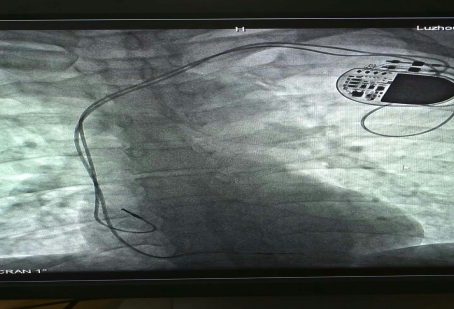

已安裝好的起搏系統

在征得患者及家屬的同意后,我院為其實施了雙腔永久心臟起搏器植入術,該手術在瀘州市市屬醫院中率先使用磁共振兼容起搏電極,為患者未來有可能接受的磁共振檢查創造了條件。

已安裝好的磁共振兼容起搏電極